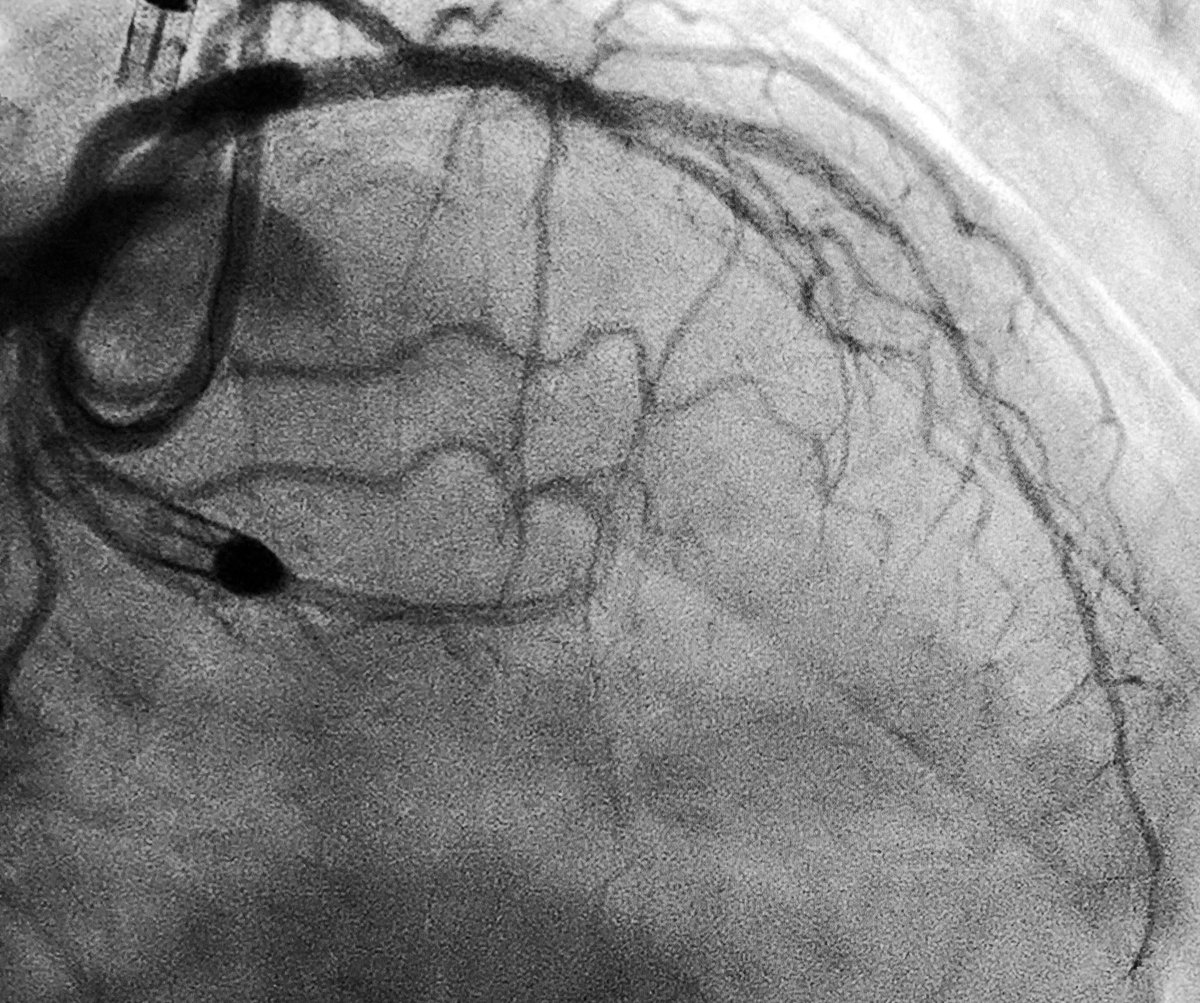

69yo lady with inferior STEMI

#radialfirst#cardiotwitter#cardioed#MedEd#accfit#somecvdpic.twitter.com/RUuklyv6noPrikaži ovu nit -